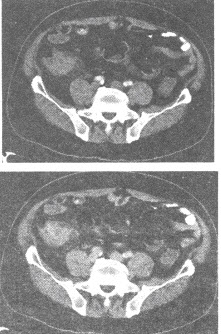

男,71岁,转移性右下腹痛4天。查体右下腹压痛,可及包块。B超示右下腹实质性占位。CT扫描如下图,最可能的CT诊断为()

A:阑尾类癌

B:回盲部增殖型结核

C:阑尾周围脓肿

D:结肠癌

E:溃疡性结肠炎